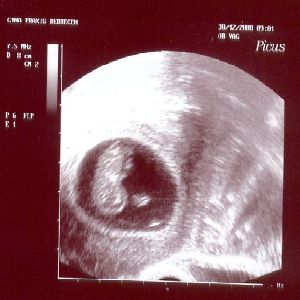

9 hét